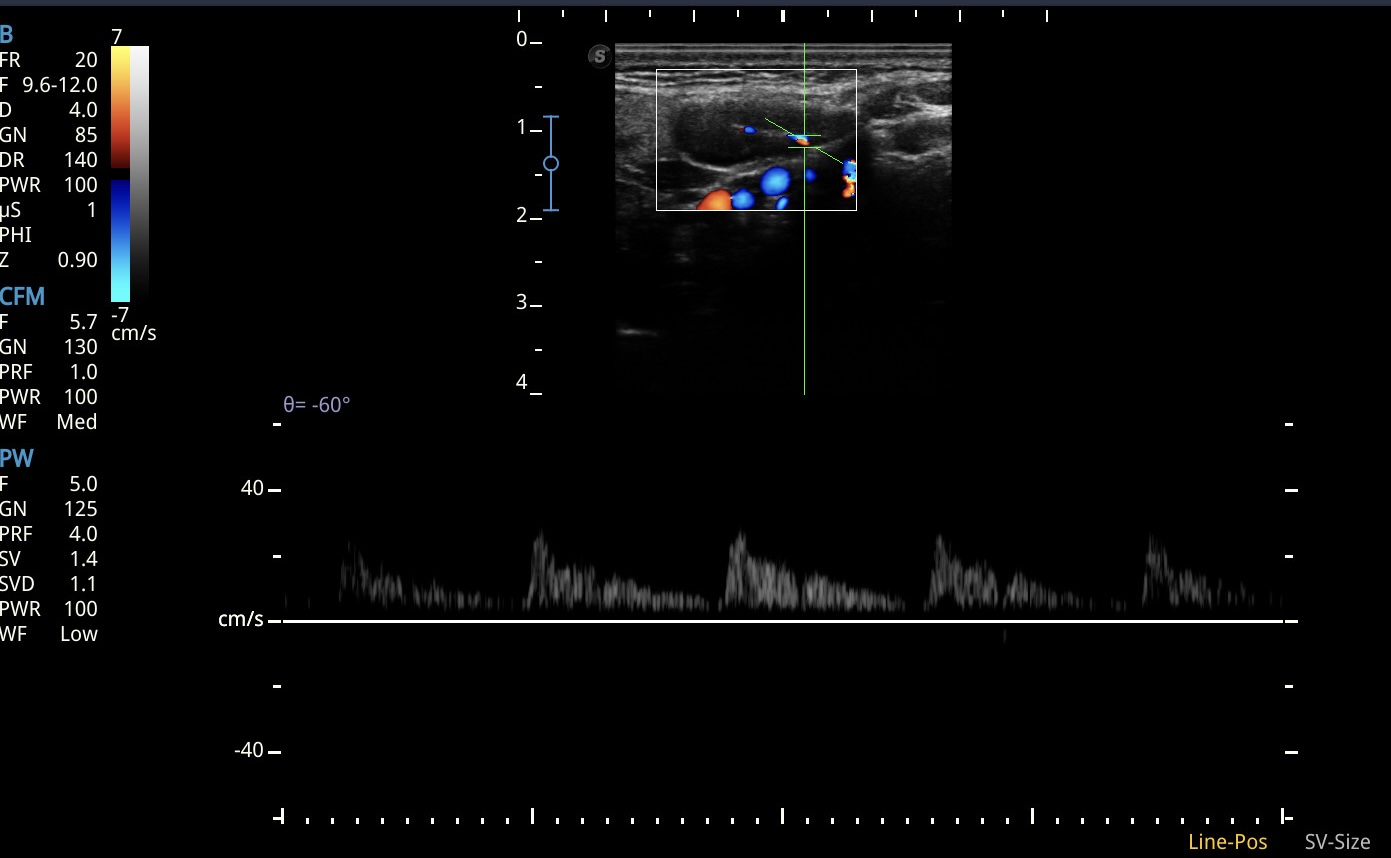

La experiencia consistió en incorporar un enfoque ecográfico metódico para la valoración de adenopatías palpadas en consulta. El protocolo se estructuró en la evaluación del eje corto, la relación eje largo/eje corto, la presencia y morfología del hilio ecogénico, la regularidad cortical, los contornos y el patrón vascular Doppler, pilares fundamentales para la estratificación ecográfica de adenopatías.

En todas las exploraciones realizadas se identificaron adenopatías benignas, mayoritariamente reactivas, en regiones cervicales, axilares e inguinales. Los hallazgos mostraron consistentemente morfología ovalada, hilio conservado, ecoestructura homogénea, cortical fina y vascularización central, características clásicas de benignidad.

Aunque en nuestra experiencia no se detectaron adenopatías con rasgos sospechosos, la aplicación sistemática del protocolo permitió buscar activamente criterios ecográficos que, de estar presentes, orientarían a sospecha de malignidad, como pérdida del hilio, engrosamiento cortical, redondeamiento, heterogeneidad marcada o vascularización periférica. La ausencia de estos hallazgos reforzó la seguridad diagnóstica y facilitó un manejo conservador adecuado al contexto clínico y a las necesidades asistenciales del paciente.